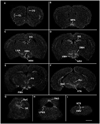

The central actions of leptin are essential for homeostatic control of adipose tissue mass, glucose metabolism, and many autonomic and neuroendocrine systems. In the brain, leptin acts on numerous different cell types via the long-form leptin receptor (LepRb) to elicit its effects. The precise identification of leptin's cellular targets is fundamental to understanding the mechanism of its pleiotropic central actions. We have systematically characterized LepRb distribution in the mouse brain using in situ hybridization in wildtype mice as well as by EYFP immunoreactivity in a novel LepRb-IRES-Cre EYFP reporter mouse line showing high levels of LepRb mRNA/EYFP coexpression. We found substantial LepRb mRNA and EYFP expression in hypothalamic and extrahypothalamic sites described before, including the dorsomedial nucleus of the hypothalamus, ventral premammillary nucleus, ventral tegmental area, parabrachial nucleus, and the dorsal vagal complex. Expression in insular cortex, lateral septal nucleus, medial preoptic area, rostral linear nucleus, and in the Edinger-Westphal nucleus was also observed and had been previously unreported. The LepRb-IRES-Cre reporter line was used to chemically characterize a population of leptin receptor-expressing neurons in the midbrain. Tyrosine hydroxylase and Cre reporter were found to be coexpressed in the ventral tegmental area and in other midbrain dopaminergic neurons. Lastly, the LepRb-IRES-Cre reporter line was used to map the extent of peripheral leptin sensing by central nervous system (CNS) LepRb neurons. Thus, we provide data supporting the use of the LepRb-IRES-Cre line for the assessment of the anatomic and functional characteristics of neurons expressing leptin receptor.